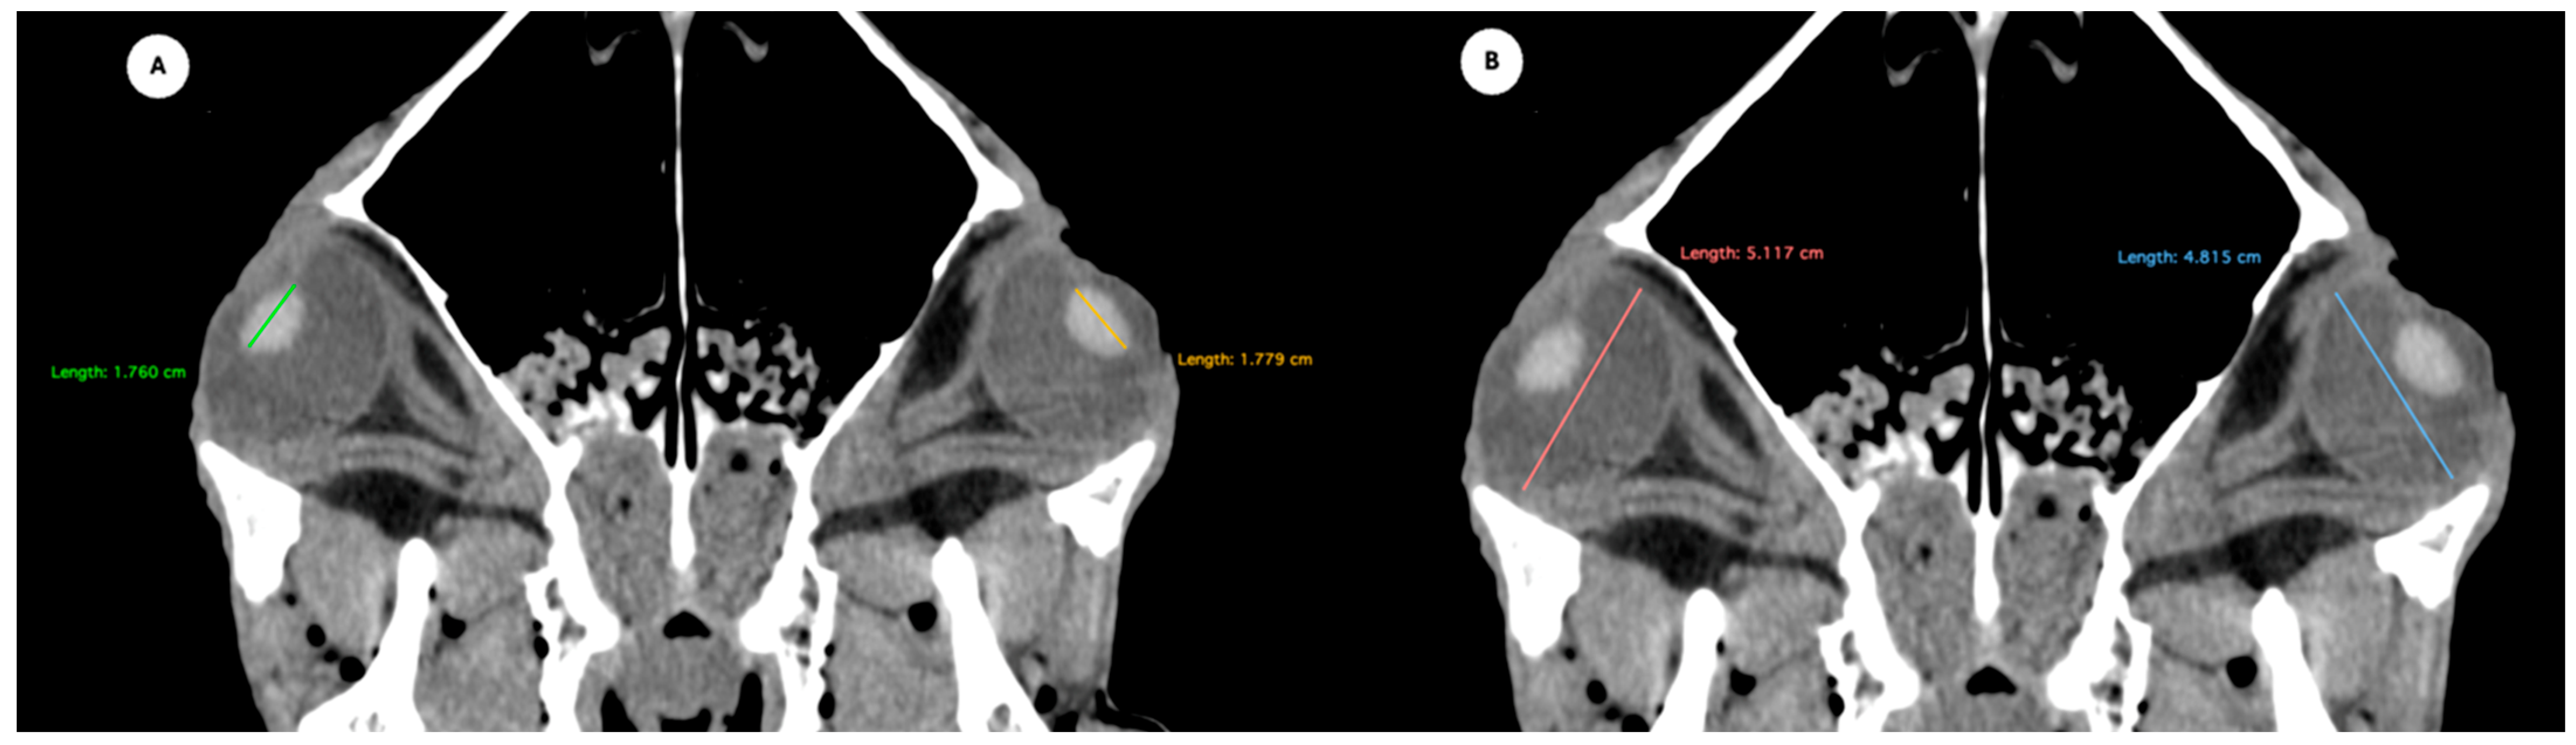

Figure 1. (A) Transverse multiplanar reconstruction (MPR) of the equine eyeball showing the maximum anterior–posterior distance (axial length), measured from the external surface of the cornea to the internal surface of choroid/retina/sclera, and the maximum latero-medial distance (equatorial width), measured perpendicular to the axial length. (B) Transverse MPR illustrating lens dimensions, with the latero-medial distance (equatorial width), measured at its widest point.

Figure 2. Dorsal multiplanar reconstruction (MPR) images showing (A) the maximal latero-medial distance of the lens and (B) the maximal latero-medial distance of the eyeball, measured perpendicular to the axial length, immediately caudal to the lens. - Orbital cavity height: Maximal dorsoventral distance of the orbital cavity at the level of the eyeball.

- Eyeball equatorial width and height: Maximal anterior–posterior distance (Figure 1A) and maximal lateromedial distance of the eyeball, measured perpendicular to the axial length (Figure 2B).